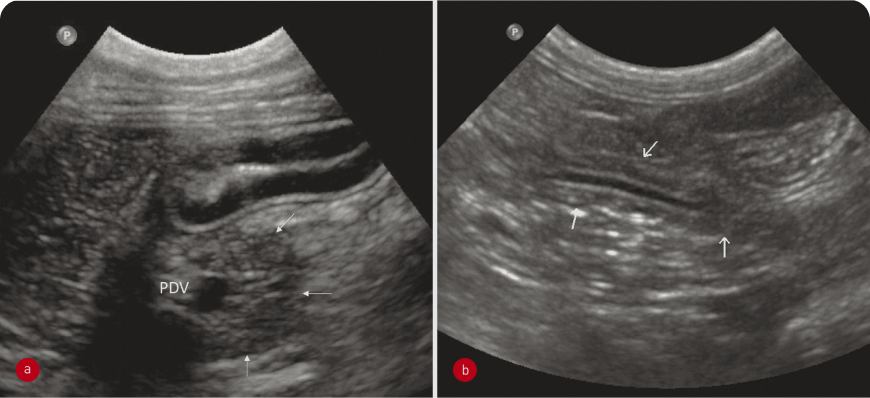

Ультразвуковое исследование позволяет визуализировать поджелудочную железу, хотя для оценки полученного изображения требуется определенный опыт. В норме поджелудочная железа дискретно гетерогенная, как правило, слегка гипоэхогенна по отношению к окружающей жировой ткани, ее границы определяются нечетко (3). У кошек она может быть изоэхогенна относительно окружающей жировой ткани, а у йоркширских терьеров – гиперэхогенна (4). При обследовании поджелудочной железы необходимо главным образом идентифицировать специфичные ориентиры. Для оценки правой доли важно визуализировать двенадцатиперстную кишку, от правой почки каудально до привратника краниально. У собаки панкреатодуоденальную вену выявить легко, она выглядит как извилистая трубчатая анехогенная структура, проходящая параллельно медиальной части двенадцатиперстной кишки (Рисунок 6a); ткань вокруг этого сосуда – это и есть поджелудочная железа. Этот сосуд удобнее визуализировать методом цветной допплерографии. У кошки в этом месте визуализируется проток поджелудочной железы и по нему можно локализовать ее правую долю. У кошек проток поджелудочной железы физиологически расширен (особенно у пожилых кошек – до 3 мм в диаметре); на уровне основного сосочка двенадцатиперстной кишки он присоединяется к общему желчному протоку. Тело поджелудочной железы расположено каудальнее привратника и вентральнее воротной вены, между желудком и поперечной ободочной кишкой.

Латерально от нисходящей ободочной кишки каудальнее дна желудка, медиальнее селезенки и краниальнее краниального полюса левой почки может визуализироваться левая доля поджелудочной железы. У кошек локализовать эту долю также можно по протоку поджелудочной железы (Рисунок 6b). У кошек можно измерить толщину поджелудочной железы, которая не должна превышать 1 см (5).